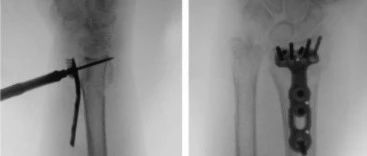

开放性骨折如何固定及创面修复?看完这篇就明白啦

开放性骨折固定骨折稳定可以通过外固定支架、髓内钉、钢板固定来实现临时或终末固定,具体的骨折固定方法取决于骨折的程度与部位,局部软组织缺损的程度以及病人的全身情况等。如果一期使用内固定治疗,必须同时满足彻底清创及软组织良好覆盖2个条件。01外固定支架固定外固定架可用于几乎所有开放性骨折的临时固定,必要时也可作为最终固定1外固定支架技术简单、安全、方便、快速、失血量小;2当需要损伤控制的情况下具有优势,例如ⅢC型开放性骨折和不稳定的多发伤患者;...